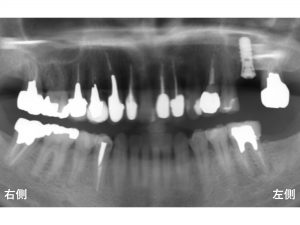

以下が治療後です。

長いインプラントを埋入することができました。

当医院で使用しているインプラントは、世界でもっとも信頼性の高いインプラントの一つであるストローマンインプラント です。